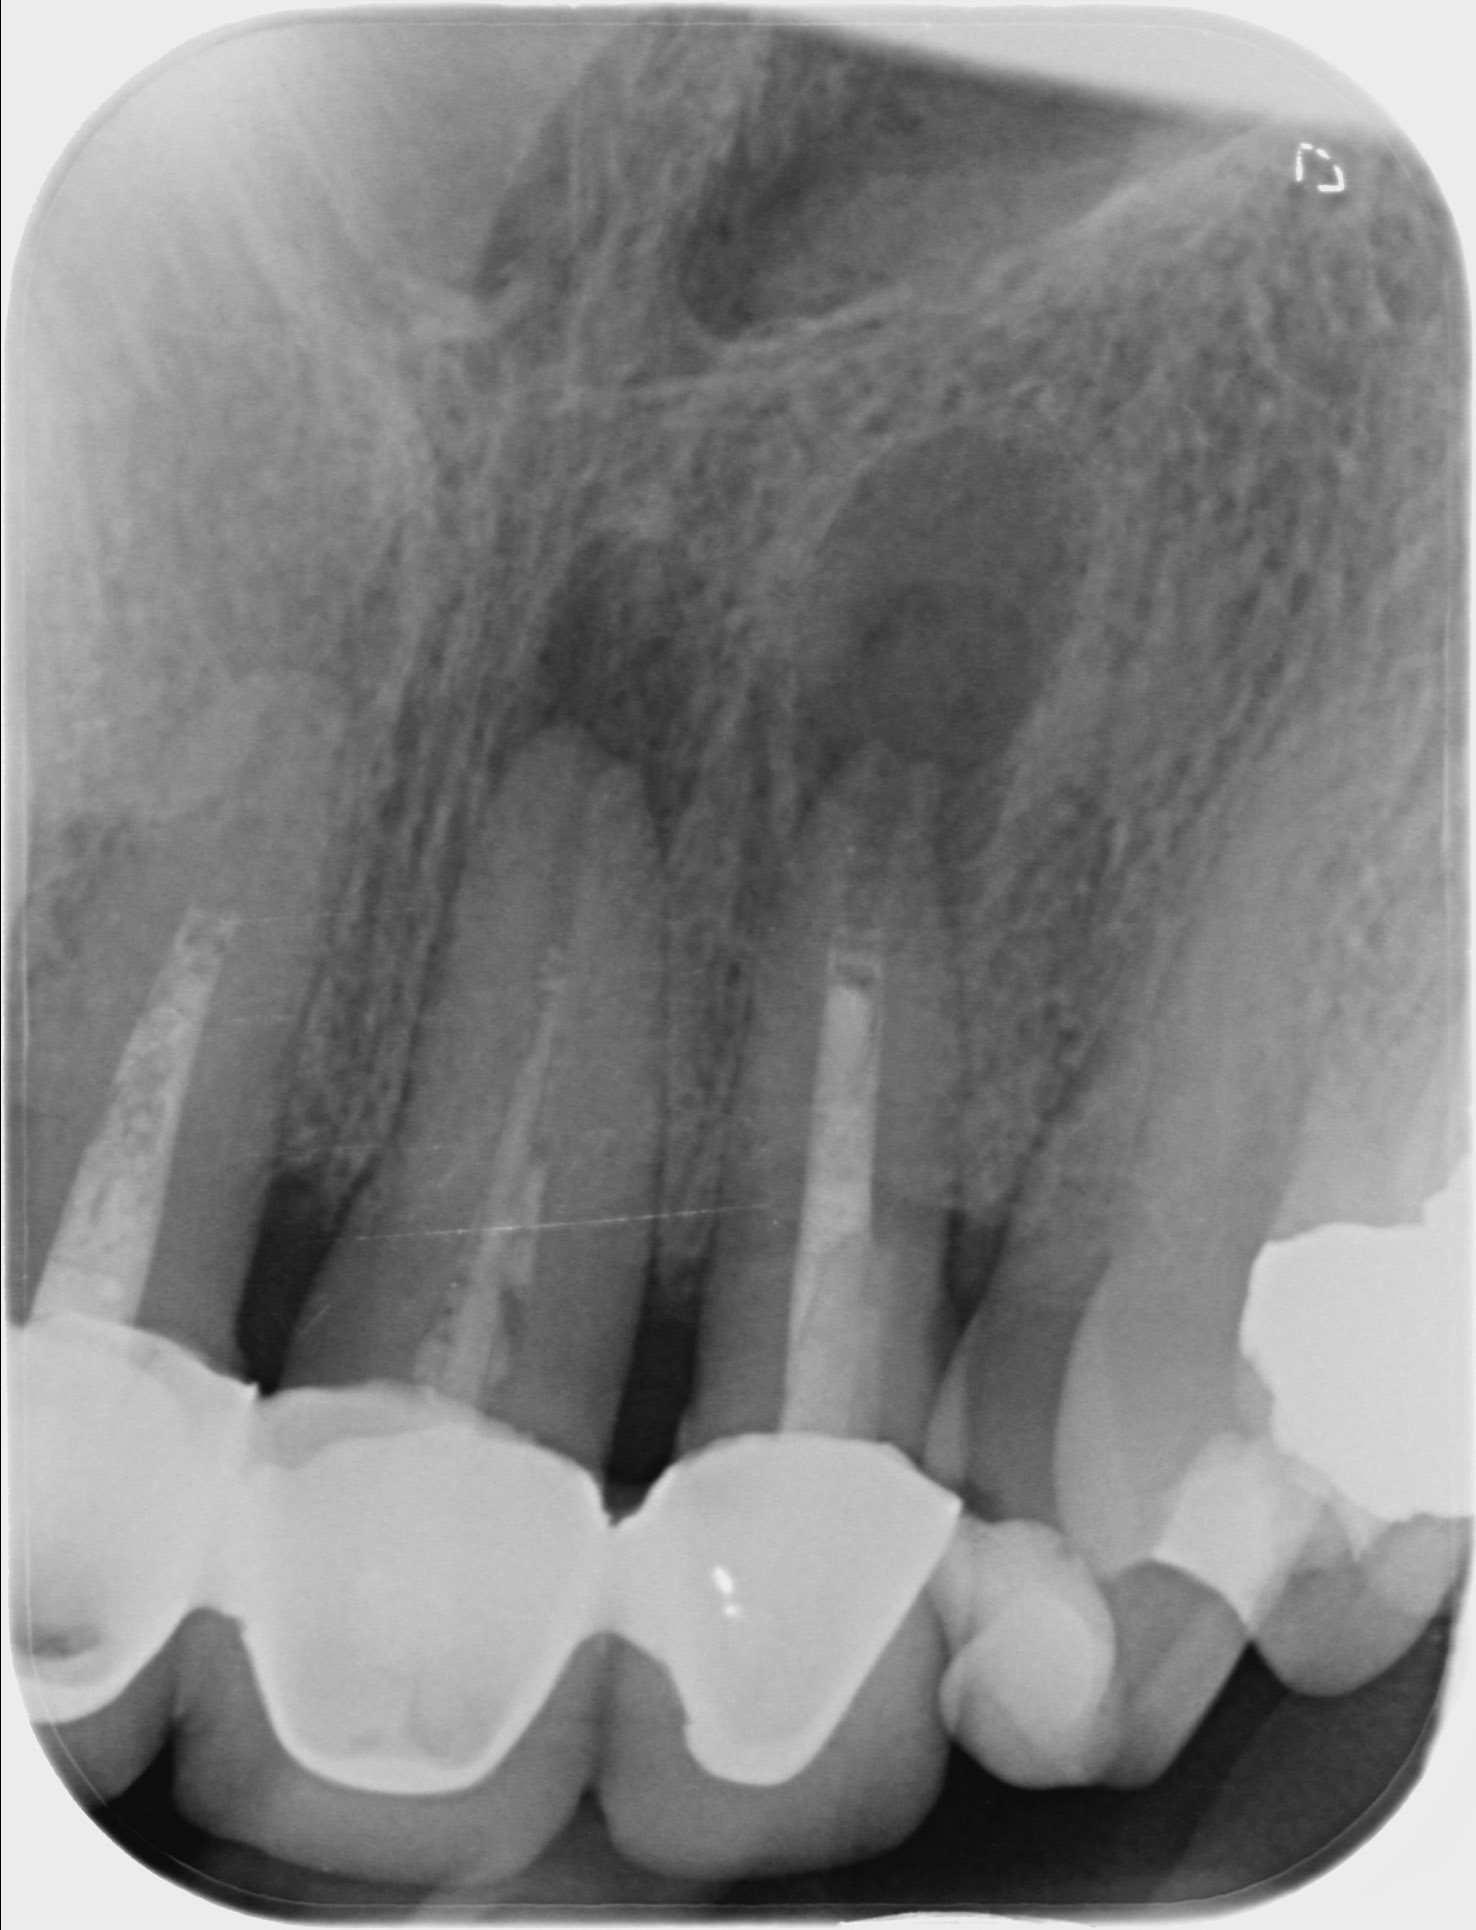

Autotransplantace

Náš zkušený tým se rád postará o všechny fáze autotransplantační léčby.